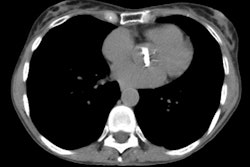

Bronchiolitis obliterans:

The patient shown below had experienced a severe right lower lobe haemophilus influenza pneumonia the preceding year, but had persistent pulmonary complains. The inspiratory CT images reveal bronchiectatic changes involving the bronchi to the anterior and medial basal segments of the right lower lobe (yellow arrows). Expiratory images deomstrate air trapping in these same segments (white arrows). Air trapping is also evident in the medial segment of the right middle lobe. The findings are consistent with post-infectious bronchiolitis obliterans.